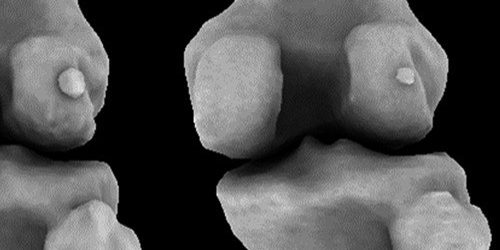

Фабелла или сесамовидная кость латеральной головки икроножной мышцы когда-то была почти утрачена людьми в ходе эволюции. Ее постепенное возвращение в течение последнего века было сюрпризом для ученых.

Новые данные, опубликованные в Journal of Anatomy могут помочь врачам лечить пациентов с болезнями коленного сустава, а также дает информацию о поздней эволюции человека. Фабеллу, которая располагается в толще коленных сухожилий, связывают с болью с коленном суставе.

Наличие фабеллы имеет свои недостатки. Она в два раза чаще обнаруживается у людей с остеоартритом. Однако неизвестно, является ли она причиной заболеваний, а если является, то каким образом. Также она сама по себе может вызывать боль и дискомфорт и мешать операции по замене сустава.

Ученые пишут, что фабеллу, вероятно, можно назвать аппендиксом скелета. В древнем мире фабелла могла служить обезьянам аналогом коленной чашечки, усиливая мышцы. Но со временем, с ходом эволюции, кость стала исчезать. Теперь, по всей видимости, она причиняет только проблемы. Однако почему она «вернулось» остается загадкой.